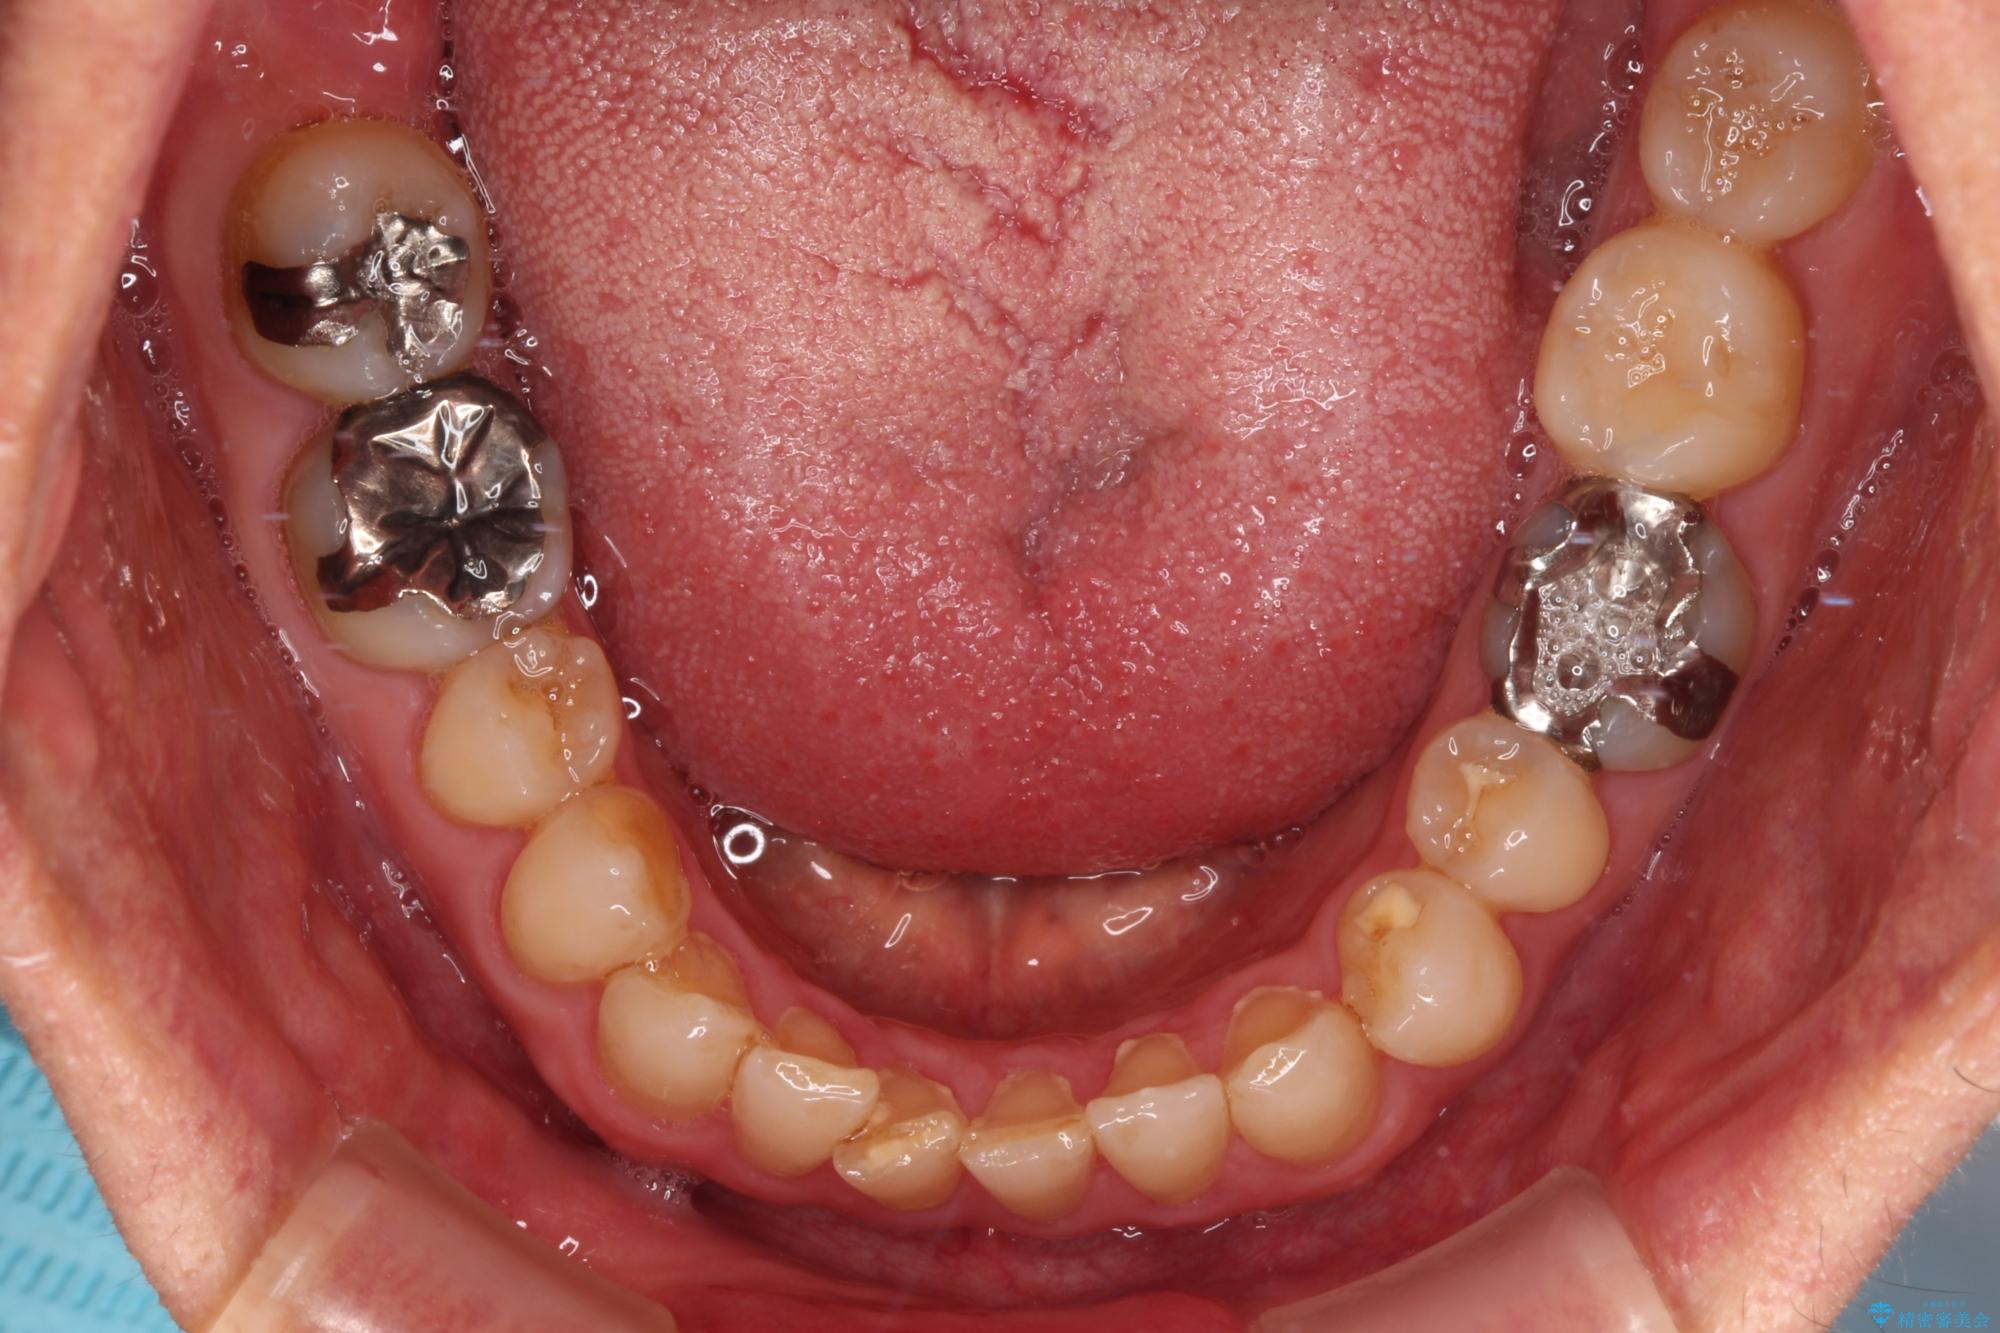

下顎前歯が隠れるほどのディープバイトにより、強い咬合力と突き上げで上顎歯列に隙間が空いている状態でした。

手前に傾斜している奥歯をワイヤー装置で立ち上がらせ、咬み合わせの高さを挙上することで突き上げを解消し、空隙歯列を改善していくこととしました。